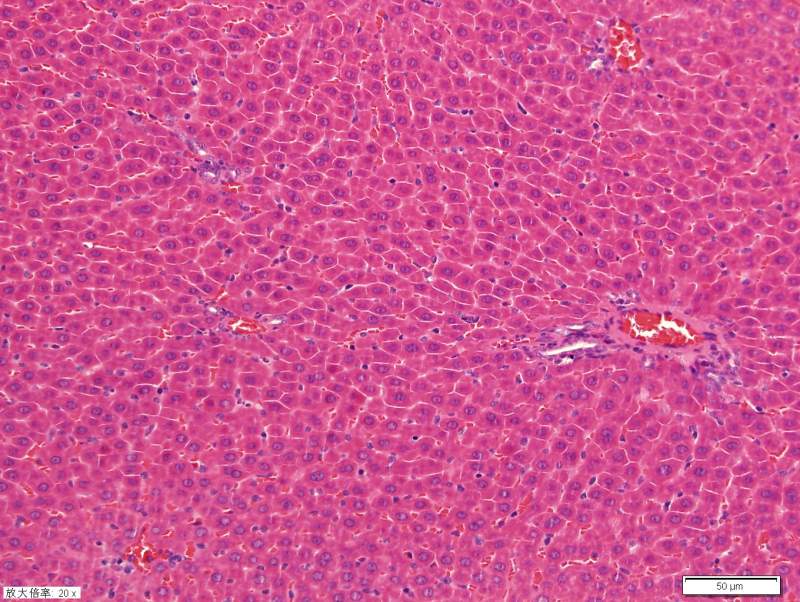

Çó¸÷λսÓѰïæ¿´¿´ÎÒÕ⼸×é¸ÎÔàHEȾɫ½á¹ûÊÇ·ñ·¢ÉúÁ˲¡±ä ûÓÐѧ¹ý²¡Àí£¬ÕæÐÄ¿´µÄһͷÎíË®¡£¡£¡£Íû¸ßÊÖÖ¸½Ì£¬²»Éõ¸Ð¼¤ 1-1.jpg 2-1.jpg 3-1.jpg 4-1.jpg 5-1.jpg 6-1.jpg 11-1.jpg |

| ÓÐÑ×֢ϸ°û£¬µ«ÊÇ¿´ÆðÀ´ÏñÊÇÕý³£¸ÎÔà×éÖ¯£¬ÁíÍ⣬ÇÐÆ¬ÓпªÁÑÏÖÏ󣬿ÉÄÜÊÇÄãʹÓõÄ×éÖ¯¹Ì¶¨ÒºÓÐÎÊÌâ¡£ |